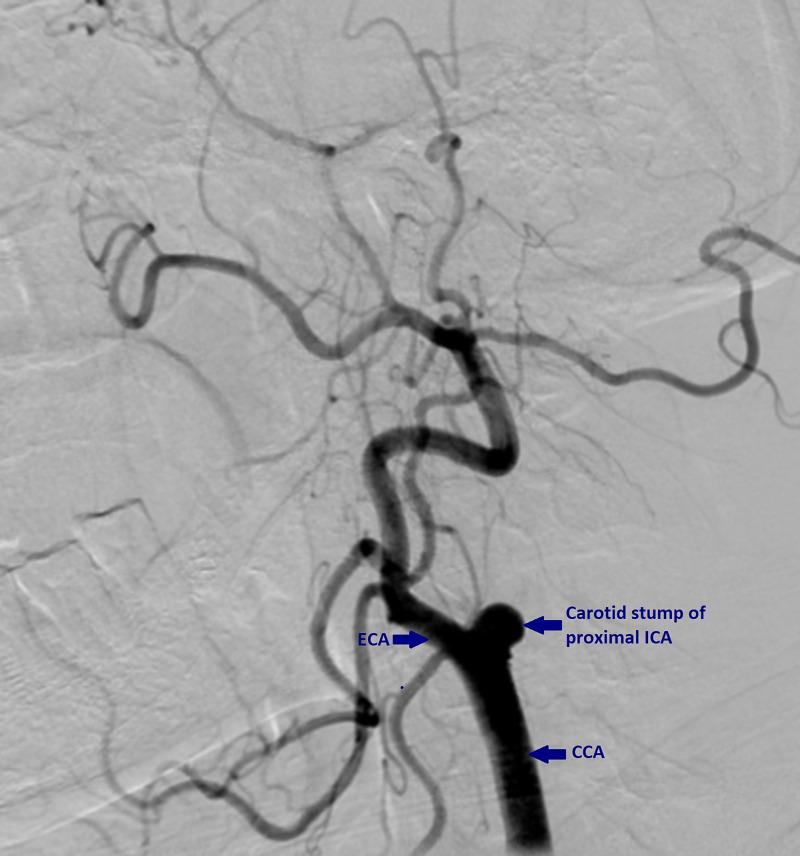

Carotid stump syndrome is a rare cause of recurrent cerebrovascular accidents. Carotid stump is the patent proximal remnant below the completely occluded internal carotid artery (ICA). Cerebral and retinal ischemic symptoms seen after complete occlusion of ipsilateral ICA is known as carotid stump syndrome. Known for causing recurrent ipsilateral cerebrovascular accidents, it is a potentially treatable entity. The therapeutic goal is medical management with a statin, dual anti-platelet therapy along with surgical intervention either with an endovascular repair or carotid endarterectomy. Herein, we present a case of carotid stump syndrome managed medically.

颈动脉残端综合征是复发性脑血管意外的罕见病因。颈动脉残端是完全闭塞的颈内动脉(ICA)下方的开放近端残余部分。同侧ICA完全闭塞后出现的脑和视网膜缺血症状称为颈动脉残端综合征。它因可导致复发性同侧脑血管意外而闻名,是一种潜在可治疗的病症。治疗目标是采用他汀类药物进行药物治疗、双重抗血小板治疗以及通过血管内修复或颈动脉内膜切除术进行手术干预。在此,我们报告一例采用药物治疗的颈动脉残端综合征病例。